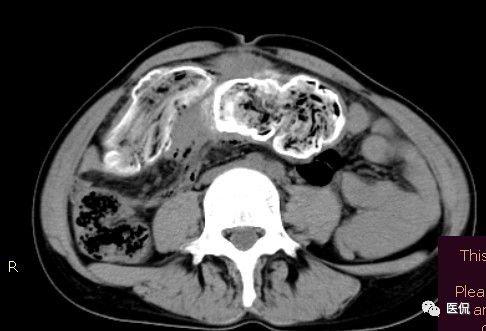

影像特点

腹腔内残留的纱布在人体内引起渗出或液化坏死并纤维包裹形成异物性脓肿(纱布瘤)。纱布瘤的影像特点:圆形或卵圆形肿块,较大,有完整包膜,薄壁,较少的情况下为厚壁,边界较完整,增强后薄膜可以持续强化。不同时期的纱布瘤可以有不同表现:早期(10个月或半年内)多表现为蜂窝状;2~5年内一般表现为囊性飘带状;10~20年之后则为实性软组织密度,包膜钙化呈钙化网状结构。手术过程中残留在人体内的医用纱布所形成的肿瘤样病变。

腹腔内遗留纱布团的影像学表现,以B超较具特征性,其主要表现为:腹腔或盆腔内特殊率减的黑色包块,后方伴有扇形衰减的声影,上窄下宽,好似一“黑色大布”,早期包块内含有不规则光团或光点,随时间延长有缩小或消失,为纱布团内气体。CT的优势在于早期常表现为软组织密度的肿块,其内可见多少不等的气泡,随时间的延长气泡逐渐被吸收减少至消失,增强扫描可见包膜不同程度强化而内容物无强化。熟悉其影像学表现,可在术前作出明确诊断。